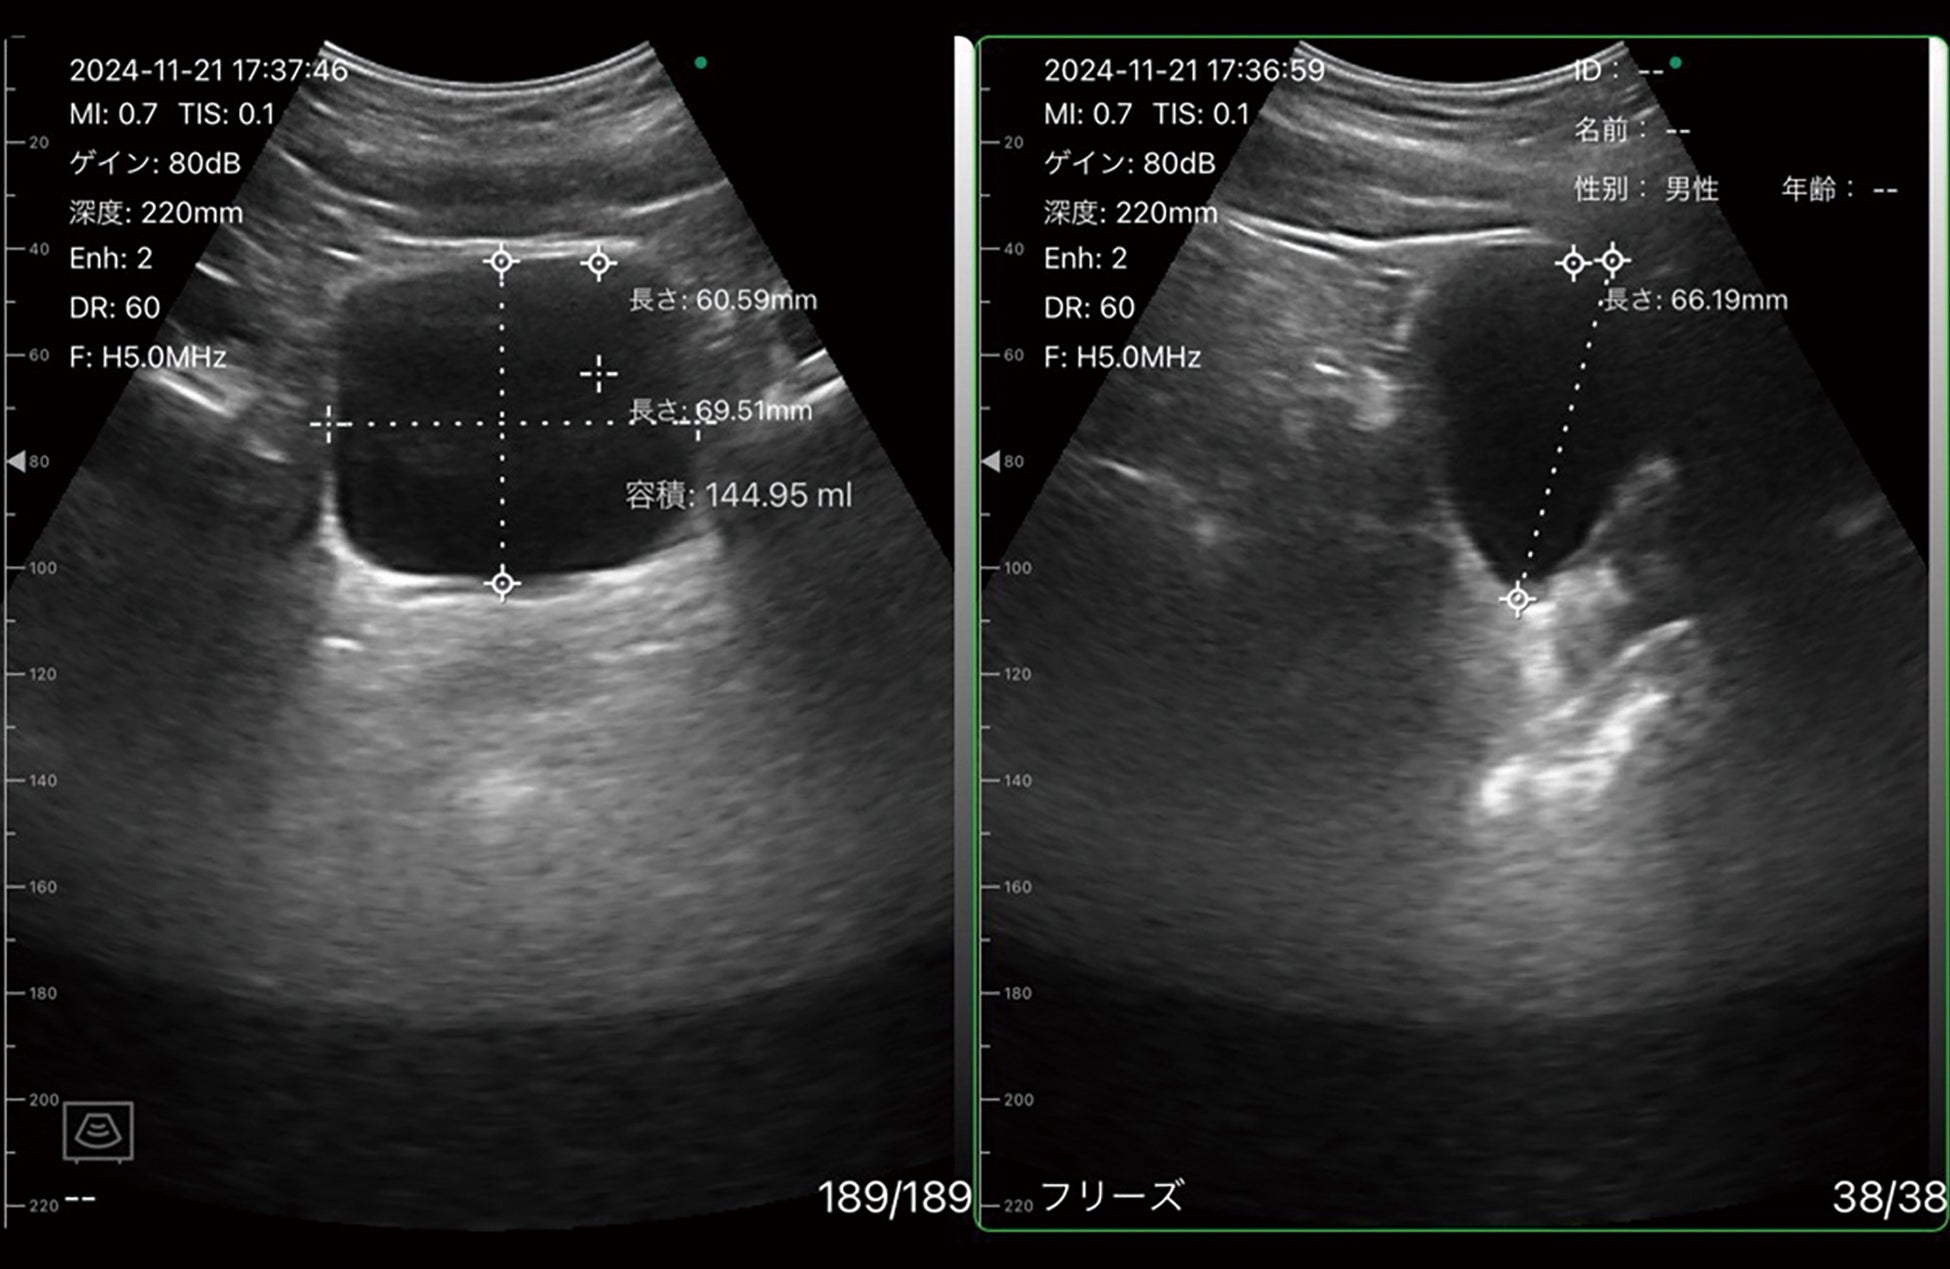

・各種計測・容積計測

ポケットエコー miruco CL5 特集サイトでは、製品コンセプト動画、デモ貸出中やユーザー向けの使用ガイド(使用説明動画)、ユーザーの声、描出画像例など、様々なコンテンツを掲載いたします。